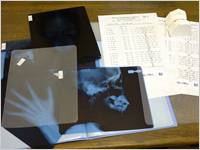

矯正治療をされると決めたら、検査のご予約のご連絡を下さい。

矯正治療をされると決めたら、検査のご予約のご連絡を下さい。

検査には、1時間から1時間30分ぐらいのお時間がかかります。 - 資料製作・分析

検査で採った歯型を作り、レントゲンなどと併せて分析を行います。

検査で採った歯型を作り、レントゲンなどと併せて分析を行います。 - 診断・治療方針の決定